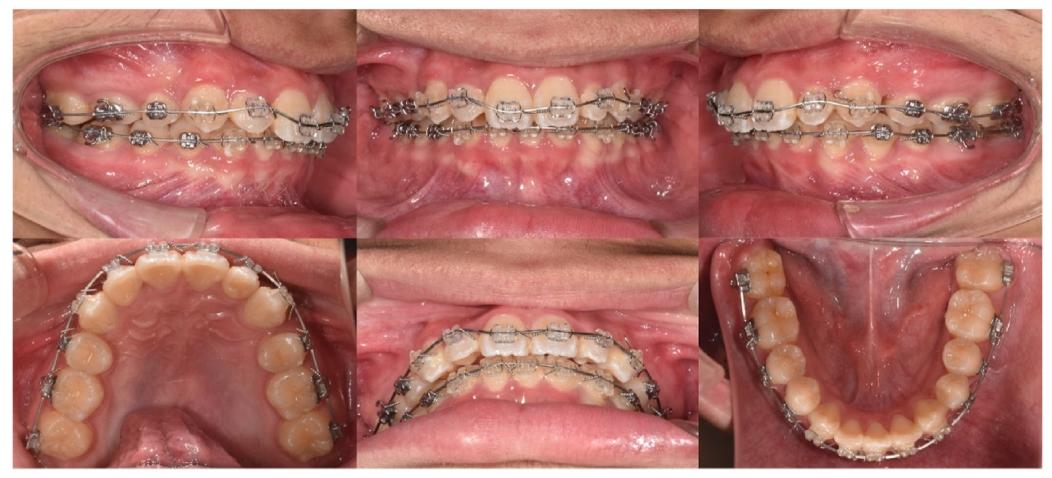

四、治疗成果:颜值与功能双提升!✅

❶ 外观改善

✅ 侧面凸度减小,唇部自然闭合,面部对称性提升

✅ 前牙覆盖从6mm降至2mm,覆合正常化

❷ 咬合重建

✅ 阻生的#12完全排齐,与对颌牙形成良好接触

✅ 反锁合解除,上下磨牙“咬合对位”,咀嚼效率提升

✅ 下牙3颗切牙以假想中线对齐,牙弓协调美观

治疗后面像对称,口内照显示整齐牙列与正常咬合

❸ 影像学验证

✅ 头影测量:上切牙唇倾度显著改善(U1-FH角从142.5°→114.9°),下颌逆时针旋转,骨性关系更协调

✅ 全景片:牙根平行度良好,牙周组织健康